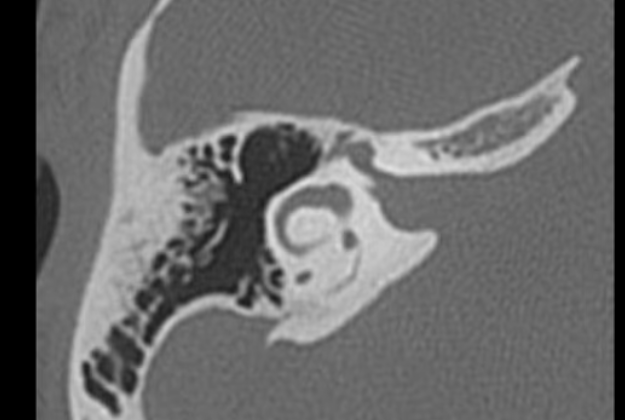

To become a skilled surgeon, mastering anatomy before surgery is crucial. Reviewing pre-operative imaging is the best way to achieve this.